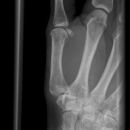

Daumen lateral (2. Ebene)

Lagerung

sitzend - seitlich zum Tisch

abgewinkelte Unterarm und Hand liegen auf

Finger 2-5 werden leicht aufgestellt

Daumen senkrecht zum Bildempfänger

Zentralstrahl

senkrecht auf Objektmitte

inkl. Grundgelenk oder Daumensattelgelenk

Qualitätskriterien

D1 soll vom Sattelgelenk bis zur Daumenkuppe rein seitlich abgebildet sein.